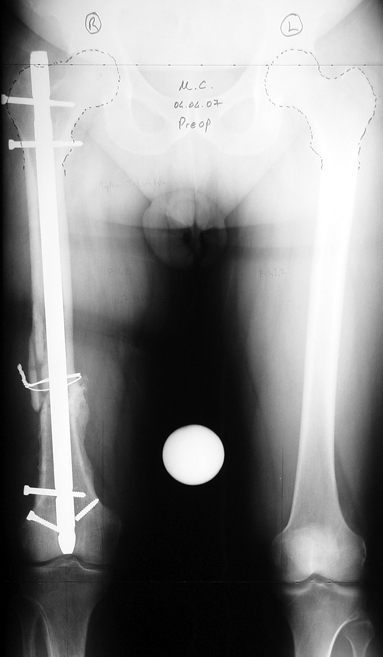

Kırık kaynama yokluklannın tedavisi hala, ortopedik cerrah için çözümü güç sorunlardandır. Tek bir tedavi yöntemi yoktur. Tüm bu yöntemler problemli ve daima komplikasyonlara açıktır. Kaynamamaya enfeksiyon, yumuşak doku kaybı ile deformite ve kısalık eşlik edebilmektedir, Kaynamama için internal ve eksternal birçok teknik belirtilmiştir. Kaynamayan kemik uçlarının çıkartılması, damarlı fibula veya fibula grefti, damarlı kas greftleri ile birlikte internal fiksasyon uygulamaları, elektrik stimulasyon gibi uygulamalar kaynamamada bir şeçenektir. Fakat kısalık ve deformite gibi ek patolojiler tedavisinde kısıtlı kalmaktadır. İlizarov eksternal fiksatörü ile uygulanan distraksiyon osteogenezi uygulamaları ile birlikte yapılan psödoartroz sahasından akut kısatma ve aynı kemikteki diğer segmentten uzatma yapılmaktadır. Ilizarov ve arkadasları, kendi geliştirdikleri yöntem ve fiksatörle, aynı anda, hastanın günlük aktivitelerini kısıtlamadan, eklem fonksiyonlarını koruyarak kaynamayı basarmıs,deformiteyi düzeltmis, uzunlugu yeniden sağlamıstır. Bu teknik sayesinde kemik defektlerinin kapatılması ve enfeksiyon gibi hastaya morbidite getiren ek patolojiler giderilmiş aynı zamanda kısalıkta telafi edilmiştir.

Management-of-Stiff-Hypertrophic-Nonunions-by-Distraction-Osteogenesis-A-Report-of-16-Cases-1.pdf